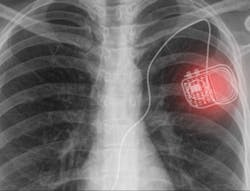

Most implantable medical devices such as pacemakers require a constant source of energy to operate, which has limitations. For example, batteries have a finite lifespan and once the battery power gets exhausted, there is no other option but to perform invasive surgery to replace the battery, which poses a risk of surgical complications such as bruising, infections, and other adverse events.